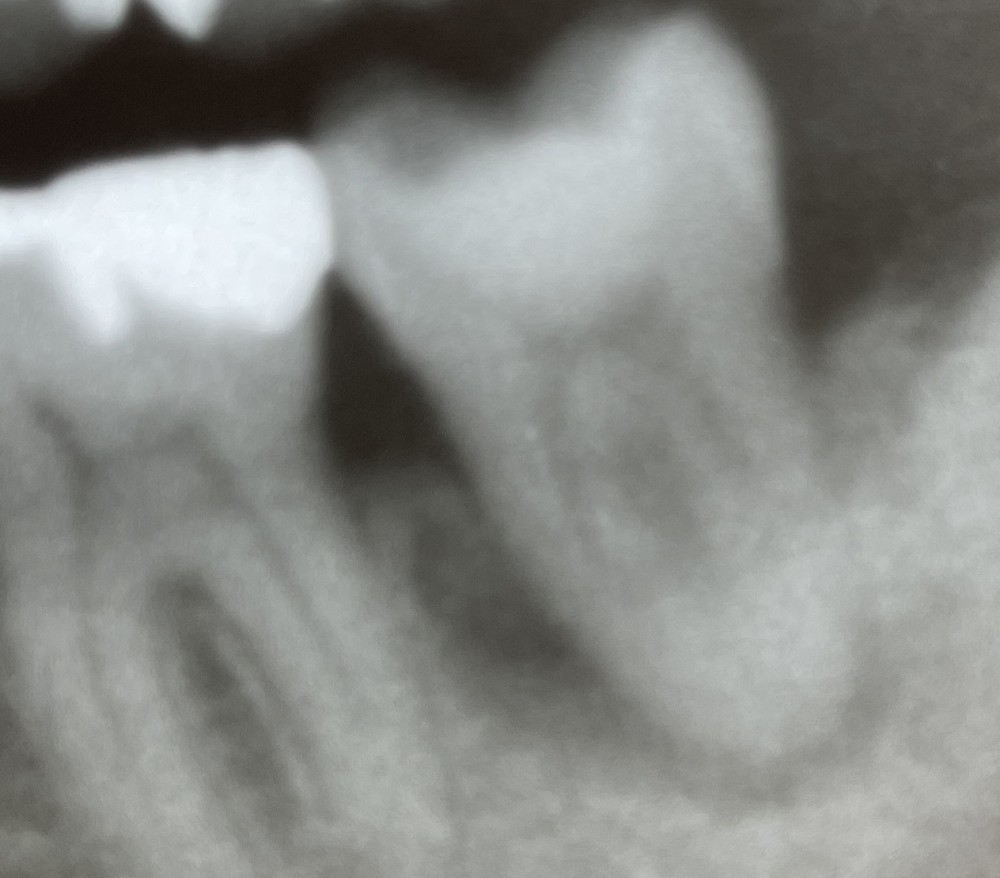

その後、2年が経過していますが、今のところ経過良好です。比較しやすいように、術前と2年経過後のエックス線写真をならべました。

(2年経過後)